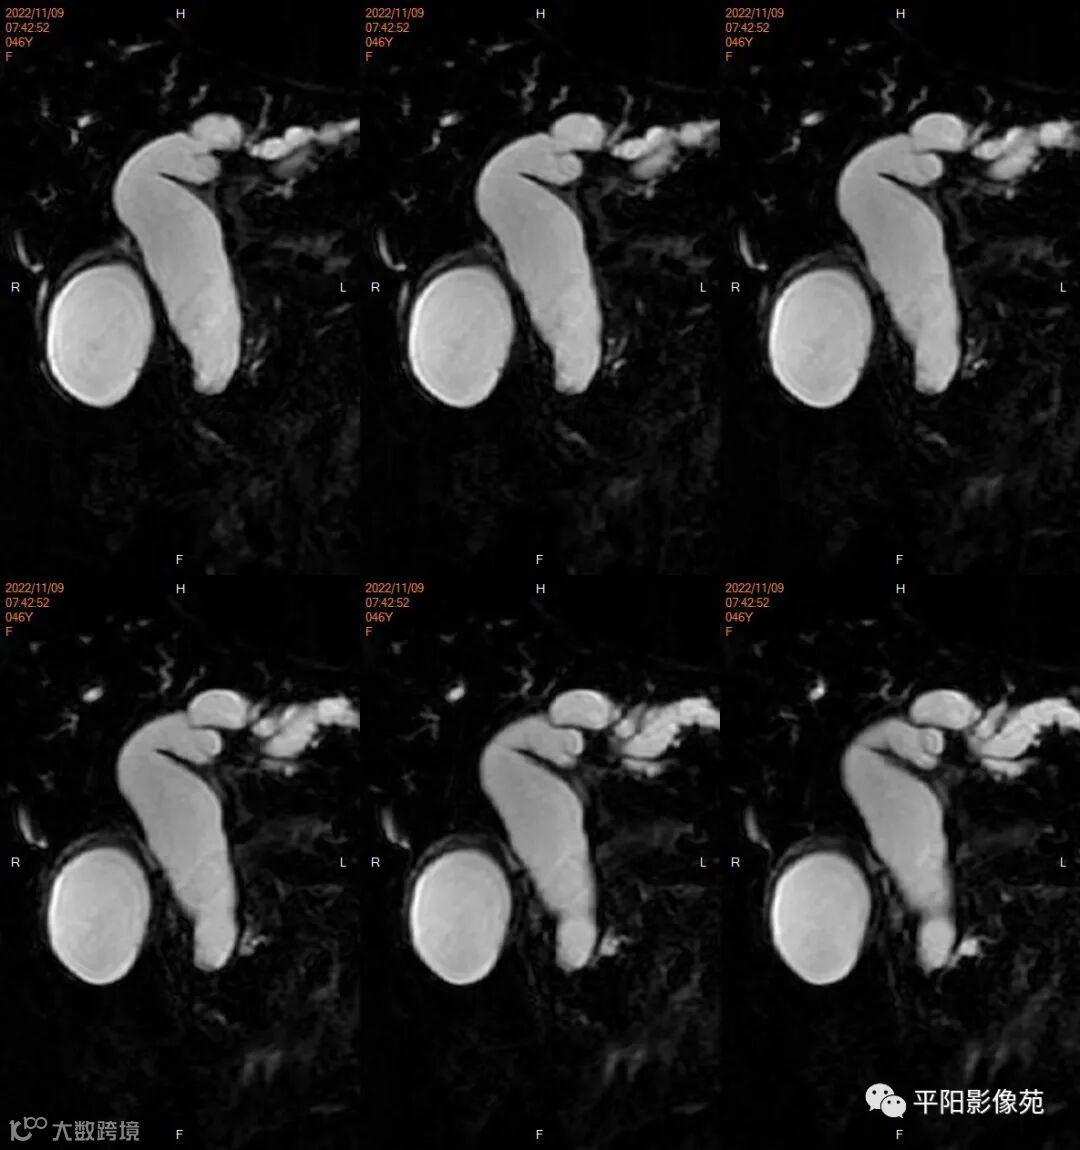

影像学检查

MR

影像表现: